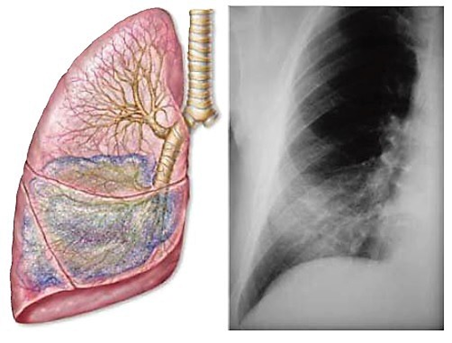

- Síndrome de condensación pulmonar.

- Normalmente, el parénquima pulmonar está lleno de aire; en estas condiciones no se transmite bien el ruido laringotraqueal ni la voz. Cuando sobreviene una inflamación o un tumor, el aire es reemplazado por secreciones organizadas o masas tumorales y el parénquima se hace más compacto o sólido , lo que cambia la transmisibilidad de los ruidos a través del pulmón.

- Sin embargo, es preciso considerar que los signos originados por estas alteraciones varían según sea la mayor o menor extensión y profundidad que alcance la condensación . Las condiciones ideales se dan cuando el foco de condensación: alcanza la superficie del pulmón; tiene un volumen mayor de 6 cm de diámetro; y se extiende desde la superficie hasta los bronquios de 3 mm de diámetro por lo menos

- Radiografía. Revela una sombra no homogénea de bordes pocos nítidos con broncograma aéreo; su tamaño y densidad dependerá del lóbulo afectado.